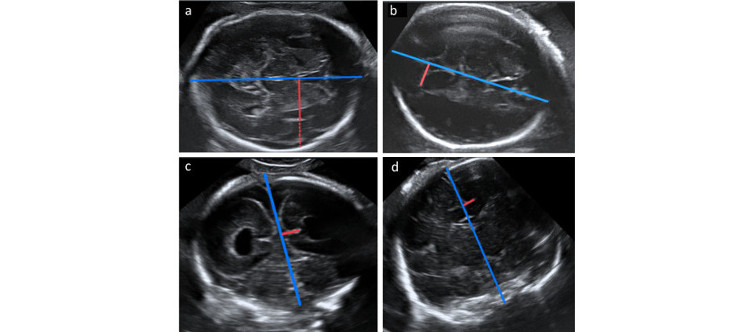

• CIBERER

La dilatación ventricular puede estar relacionada con cambios en el desarrollo cortical en los fetos con ventriculomegalia aislada

10/04/2018